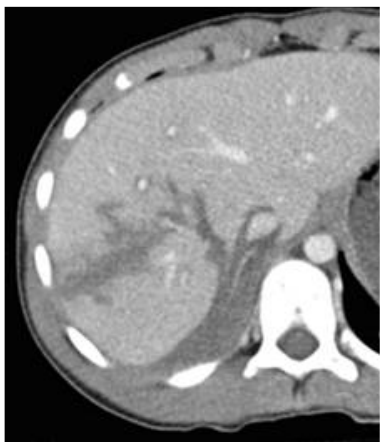

33. 五十歲阿嬤騎機車載三歲小男孩坐在前面,在十字路口被汽車從右方撞倒,緊急送醫後發現 阿嬤右大腿骨折,小男孩有右腹擦傷,小男孩受驚嚇不停哭鬧,全身冒汗,血壓95/55 mmHg,心跳數每分鐘130下,Hb 10.5 g/dL,電腦斷層檢查如下圖所示,下列敘述何者正 確?

(A)此幼兒為右腎撕裂傷 (B)幼兒有大量失血,需馬上輸紅血球補充 (C)若幼兒血行動力方面穩定(hemodynamic stable),可嘗試非手術(non-operative)的支 持療法 (D)此時宜進行緊急開腹手術